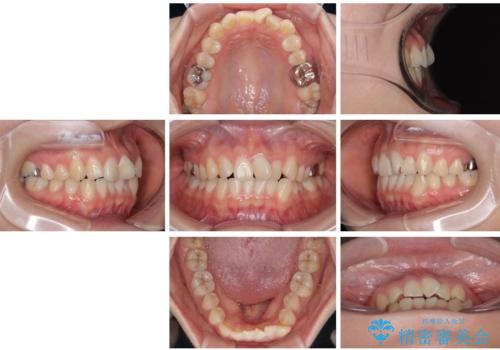

診察の結果、上下の前歯部に**叢生(そうせい/歯のガタガタ・重なり)**が認められました。

特に上の前歯にはねじれや重なりがあり、審美的にも清掃性にも影響している状態でした。

治療方法としては、装置の目立ちにくさと費用面のバランスを考慮して、プラスチック製のクリアブラケットとメタルワイヤーを組み合わせた矯正装置を使用することにしました。

また、上顎前歯の重なっていた部分にはむし歯が見つかり、治療中に適切な処置を行っています。

矯正治療期間はわずか10か月と、比較的短期間で終了しました。

前歯のデコボコがなくなり、見た目の印象が大きく変わっただけでなく、歯磨きがしやすくなり、むし歯や歯周病のリスクが大きく減少しました。